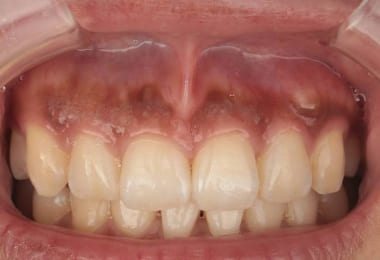

Before

1週間後

After